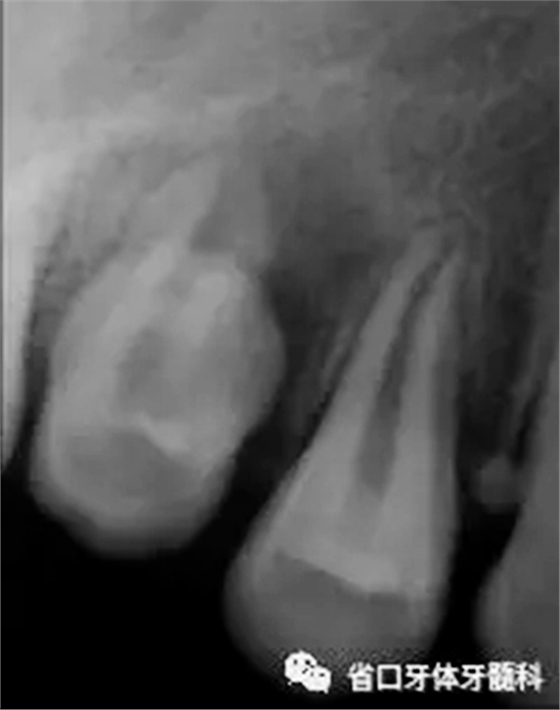

檢查: 15已萌,牙體透出暗黑色,表面局部白堊斑紋,牙體形態(tài)異常(與對側(cè)同名牙相比,腭尖較短,腭側(cè)見一淺溝,探針探不入),未探及軟腐質(zhì),未見可疑中央尖折斷痕跡,叩+,松動I°,腭側(cè)牙齦腫脹,刺破后溢膿,腭側(cè)正中PD=6mm。

圖1 口內(nèi)見15腭側(cè)膿包

圖2 根尖片(2016-3-19),15未完全萌出,形態(tài)異常, 根尖周和根側(cè)方見低密度影,牙槽骨破壞